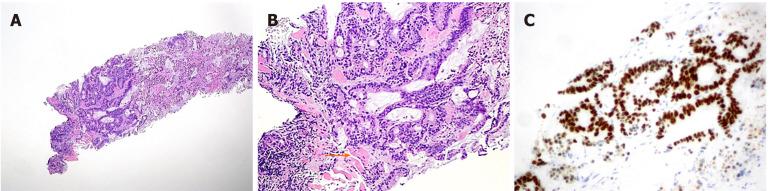

We report a case of synchronous massive breast metastasis from CRC in an 85 year old patient who came to the hospital presenting a huge mass originating from the axillary extension of the right breast. A whole body computed tomography also showed a mass in the right colon. The patient underwent a simple right mastectomy along with right hemicolectomy. The resected breast showed massive metastasis from CRC with intense and homogeneous nuclear CDX2 staining, while the colon specimen revealed poorly differentiated adenocarcinoma stage pT4a pN0 pM1 (breast) (Tumor Node Metastasis 2017). Three months later she developed a subcutaneous mass at the site of the previous mastectomy. An ultrasound guided biopsy was carried out again and revealed a metastasis from CRC. The patient then started treatment with capecitabine plus bevacizumab, obtaining stable disease (RECIST criteria) and a clinical benefit after 3 mo of therapy.

我们报告一例85岁患者发生同步性CRC乳腺巨大转移的病例,该患者因右乳腋窝延伸处出现巨大肿块前来就诊。全身计算机断层扫描还显示右结肠有一个肿块。患者接受了单纯右乳房切除术及右半结肠切除术。切除的乳腺显示有CRC的大量转移,核CDX2染色强烈且均匀,而结肠标本显示为低分化腺癌,分期为pT4a pN0 pM1(乳腺)(2017年肿瘤淋巴结转移分期)。三个月后,她在先前乳房切除部位出现皮下肿块。再次进行超声引导下活检,结果显示为CRC转移。然后患者开始接受卡培他滨加贝伐单抗治疗,治疗3个月后病情稳定(根据实体瘤疗效评价标准)并获得临床获益。